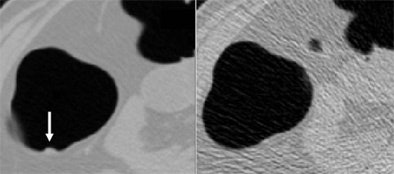

| A 6-mm polyp is visible in standard-dose CTC (left) but invisible in low-dose CTC (right). Consequently, the polyp was not detected by radiologists or CAD in low-dose CTC. Images courtesy of Dr. Masanori Imuta and Dr. Hiro Yoshida. |

No statistically significant difference in the detection rate was seen between the standard- and low-dose protocols, however CAD with low-dose data performed poorly in detecting smaller lesions, Imuta said.

"The CAD scheme has the potential to detect colorectal lesions in patients with high sensitivity and a low false-positive rate, even on ultra-low-dose CTC," Imuta said. "However, sensitivity for detecting polyps 5-10-mm in size at 20 mAs was significantly lower (p < 0.05) than that at 100 mAs," the group wrote in an abstract.